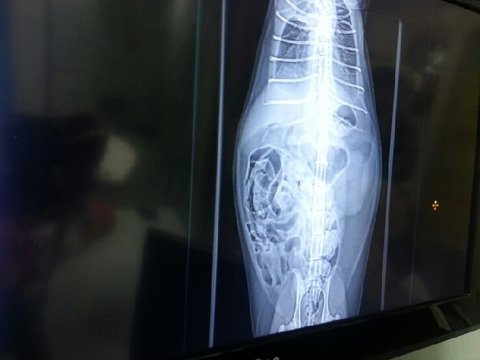

병원에서 여러가지 검사를 통해서 '복막염'진담을 받았어요...

진료 받는 내내 둥이는 참으로 얌전했어요...

x- ray 에 흉수가 차 있는게 보여요...

그리고 코로나 바이러스에서도 '양성'판정이 나왔어요....

얇은 선이 하나더 보이네요... 두줄...

복막염은....

치료법이 없습니다...

고양이에게 복막염  판정은  곧  '시한부'입니다.

인간이 복막염 고양이에게 해 줄 수 있는건... 조금 더 삶을 연장해 주는 것 말곤 없습니다.

복막염은  wet 와 dry 로 나뉘는데..둥이는 wet 입니다.

예후가 더 좋은.... dry 일 경우...6개월 최장1년 까지도 더 살아남는 경우도 있다고 했습니다.